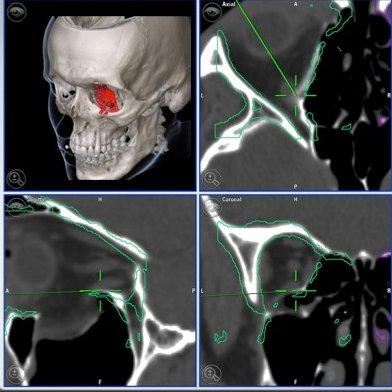

Planificación 3D reconstrucción órbita

Es necesario reparar las paredes de la órbita, reposicionar el hueso malar y liberar los músculos oculares si están atrapados en la fractura de la órbita ocular. Se puede acceder a los huesos a través de incisiones ocultas dentro del párpado o a través de la mucosa de la boca. El paciente suele estar ingresado 48 horas. El tiempo de recuperación de una fractura de órbita depende en ultima instancia de la intensidad del traumatismo, del grado de desplazamiento del ojo y del tiempo transcurrido desde el accidente hasta la intervención.

En MAXILOFACE tenemos tres objetivos de tratamiento: eliminar la visión doble, normalizar la posición del ojo y restablecer el volumen del pómulo.